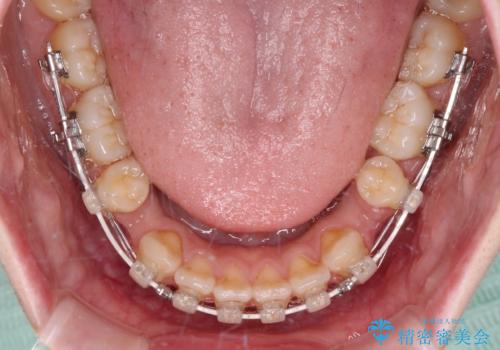

- ハーフリンガル

上下前歯が嘴のように前方に突出しており、唇が閉じにくい状態であったため、上下左右の第一小臼歯4本を抜歯して、口元の突出感を改善することとしました。

目立たない装置を希望とのことで、上顎が裏側、下顎が表側のハーフリンガル装置を用いることとしました。